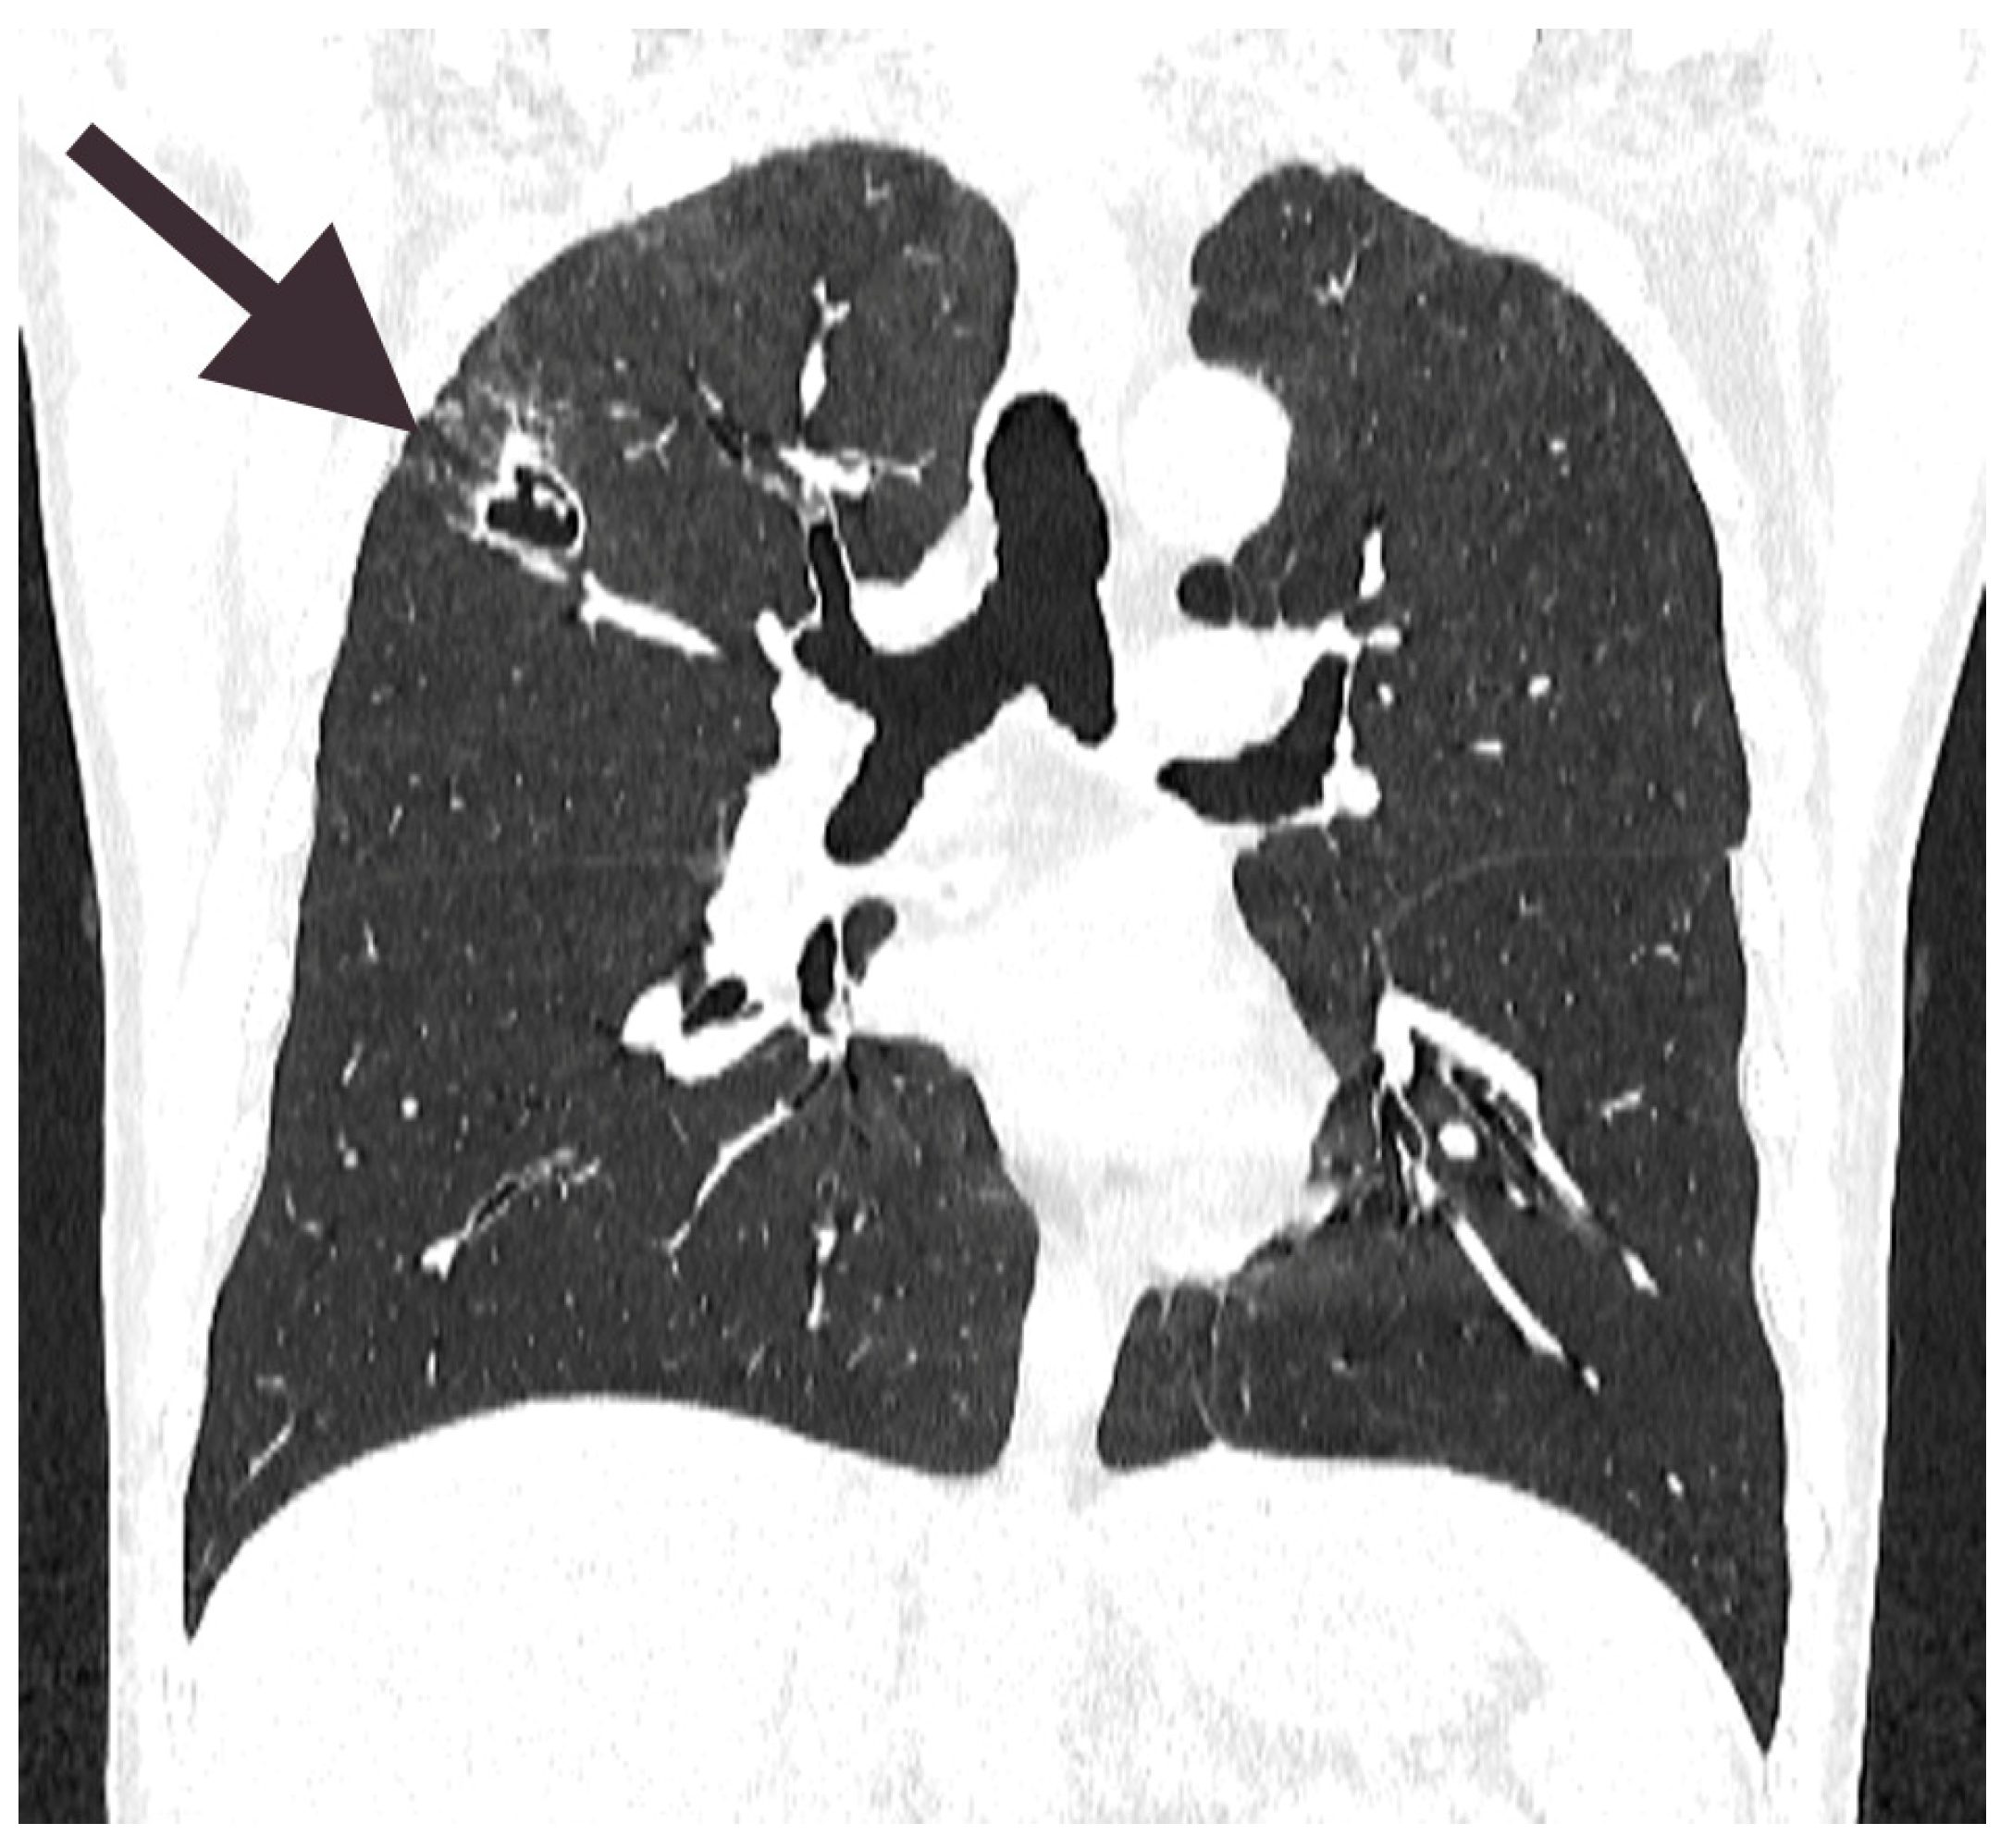

2.1. Patient’s Medical History and Clinical Course of the Disease